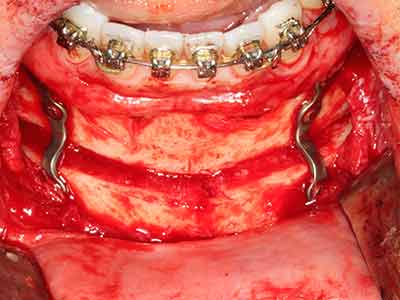

Bei der Knochenblockentnahme zeigen sich weitere Vorteile für die Piezochirurgie: Neben der bereits beschriebenen hohen Präzision bei der Osteotomie stellt sich gerade die Verwendung der dünnen Sägespitzen als besonders materialschonend heraus. Bei der Verwendung insbesondere von Lindemannfräsen sind mit deutlich höheren Entnahmeverlusten durch die dickere Instrumentenspitze zu rechnen (Lakshmiganthan, Gokulanathan et al. 2012). Die insbesondere bei retromolar entnommenen Blocktransplantaten notwendige basale Abtrennung wird durch speziell hierfür vorgesehene rechtwinklige Sägen erleichtert, so dass die Piezochirurgie als präzises, übersichtliches und sicheres Verfahren zur retromolaren Knochenblockgewinnung angesehen wird (Happe 2007) (Abb. 1-12).

Indikation: Bone Splitting